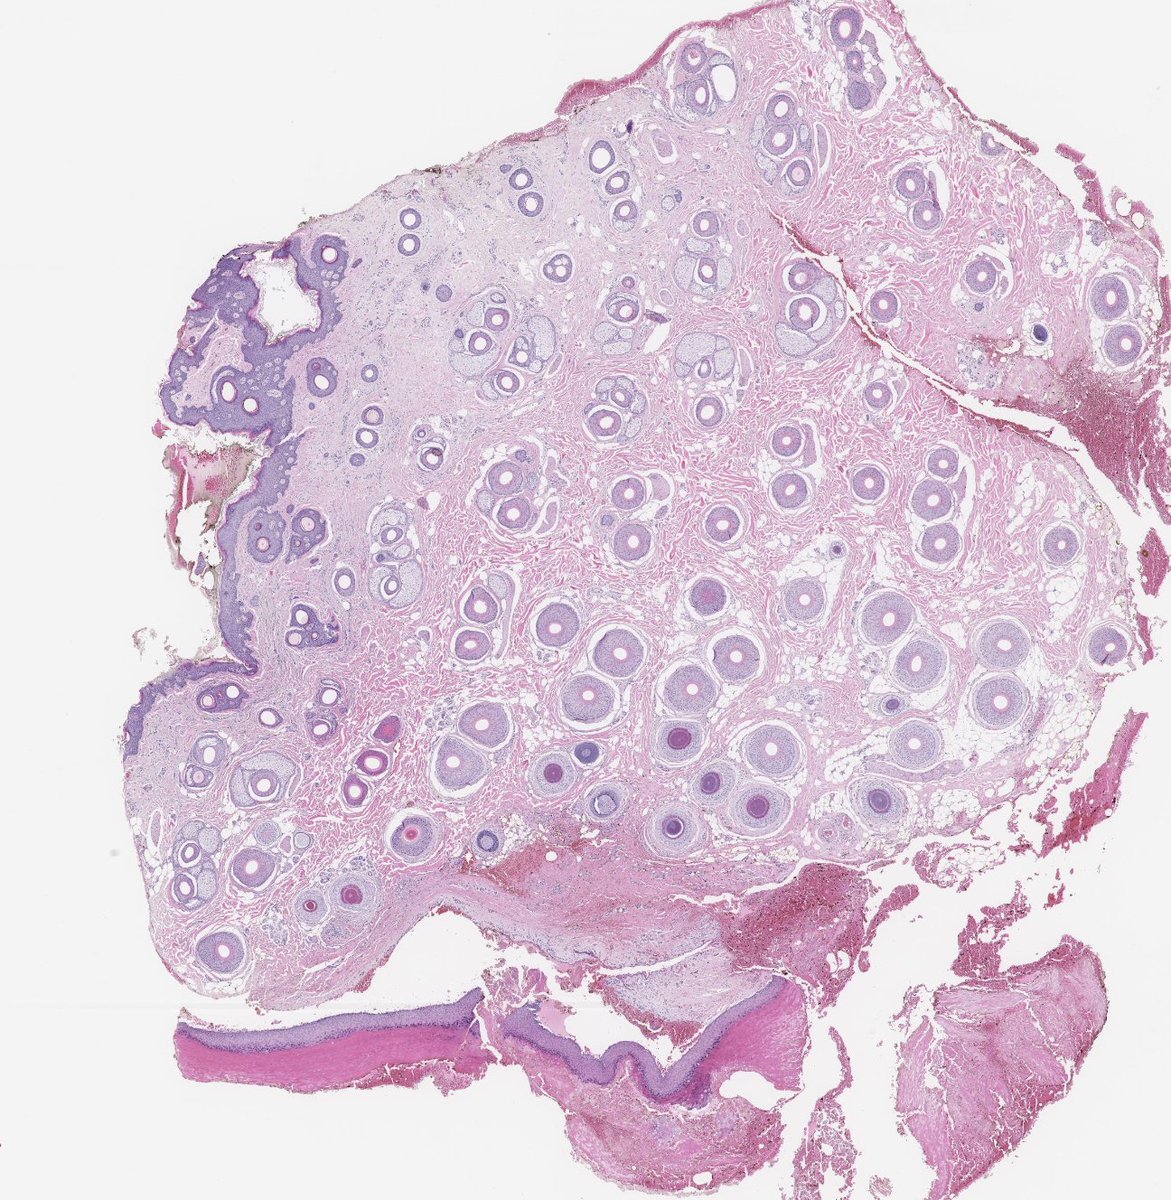

Couldn't be more excited to announce the launch of pathlibrary.com, the virtual slide site I wish had existed during my pathology residency. You can:

- See annotated histologic features